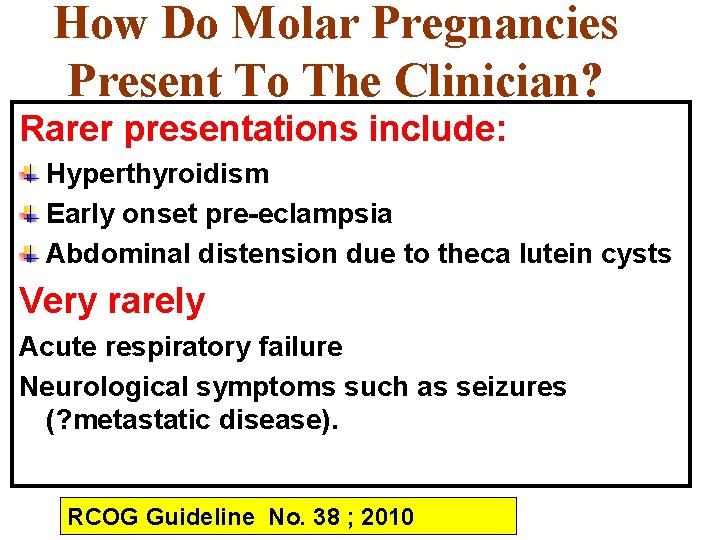

How Do Molar Pregnancies Present To The Clinician? Rarer presentations include: Hyperthyroidism Early onset pre-eclampsia Abdominal distension due to theca lutein cysts Very rarely Acute respiratory failure Neurological symptoms such as seizures (? metastatic disease). RCOG Guideline No. 38 ; 2010